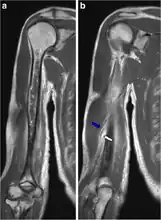

-

Chest X-ray pneumonia -

CT pneumonia -

X-ray pneumococcal osteomyelitis -

MRI pneumococcal osteomyelitis